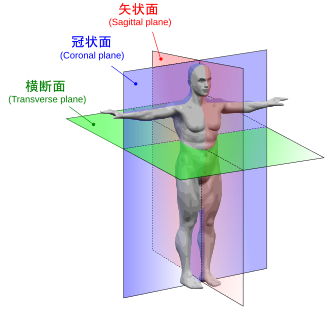

矢状面、冠状面、水平面が分からない? これで完全理解!! 身体の方向をあらわす3つの基準面 矢状面、冠状面、水平面 、本当に理解している?ここって、結構間違えやすい部分だよね。 なので、今回は「矢状面 正中面 」「冠状面」「水平面」のそれぞれの覚え方を。

矢状面、冠状面、水平面が分からない? これで完全理解!! 身体の方向をあらわす3つの基準面 矢状面、冠状面、水平面 、本当に理解している?ここって、結構間違えやすい部分だよね。 なので、今回は「矢状面 正中面 」「冠状面」「水平面」のそれぞれの覚え方を。

人体の基準面で矢状面 と 冠状面 がごっちゃになる人へ。 このイラストのイメージがあると記憶に残ります。

矢状面、冠状面、水平面が分からない? これで完全理解!! 身体の方向をあらわす3つの基準面 矢状面、冠状面、水平面 、本当に理解している?ここって、結構間違えやすい部分だよね。 なので、今回は「矢状面 正中面 」「冠状面」「水平面」のそれぞれの覚え方を。

矢状面、冠状面、水平面が分からない? これで完全理解!! 身体の方向をあらわす3つの基準面 矢状面、冠状面、水平面 、本当に理解している?ここって、結構間違えやすい部分だよね。 なので、今回は「矢状面 正中面 」「冠状面」「水平面」のそれぞれの覚え方を。

horizontal sagittal and coronal planes水平面,矢状面,冠状面 _sigittal coronalhorizontal之间的区别-CSDN博客。

DENTALISH歯科英語チャンネル🦷 ▶︎Anatomical plane 解剖学的平面CTなどでよく見かける三次元平面に関してです! ↔️体を左右に分ける面 矢状面:Sagittal plane 縦断面:Longitudinalplane ↕️体を上下に分ける面 軸断面:Axial planeInstagram。

人体の3つの基準面 矢状面・冠状面・水平面.組織細胞ゴロー .体のしくみ医療系学生の勉強垢看護学生の勉強垢鍼灸科理学療法学科作業療法士の勉強垢解剖生理学ノート解剖学講座生理学ノート国試過去問柔整科歯科衛生学生ナース。

分清frontal plane 额状面 、coronal plane 冠状面 、transverse plane 横断面 、sagittalplane 矢状面 -CSDN博客。

关于医学影像中的轴位面 横断面 、冠状面、矢状面的解释_ct轴位和冠状位的区别-CSDN博客。

医学图像的三个主要平面:矢状面、冠状面、横断面_冠状面和矢状面示意图-CSDN博客。